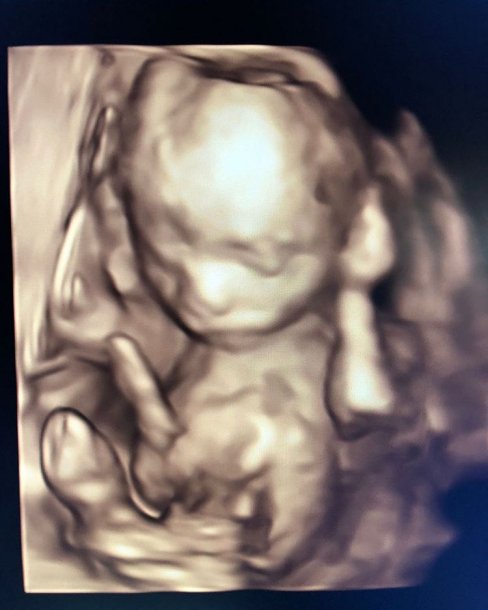

Vicky Xipolitakis transita la semana 18 de embarazo y compartió con sus seguidores la ecografía donde se nota a la perfección el rostro de Salvador Uriel. Muy contenta, la modelo mostró que, según una aplicación, el bebé mide entre 12 y 14 centímetros y pesa 150 gramos.

“Y con ustedes, les presento al milagro de cuatro meses: @salvadorurielok Hoy cumple 18 semanas, ya mide como un pimiento y me regalo estas imágenes; es la primera vez que le conozco la carita y no quería dejar de compartirlo con ustedes” #SeMeExplotaElCorazónDeFelicidad ¿Lo ven parecido a mí?”, escribió Vicky en su cuenta de Instagram.